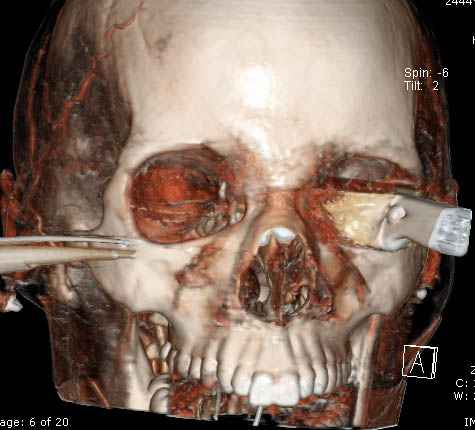

По протоколу сделаны все необходимые исследования: рентген, ангиограмма с 3Д реконструкцией, где обнаружили что все жизненно важные сосуды не задеты, даже некоторые "сидят" изгибаясь на ноже.

Одним махом нож удалить не удалось, пришлось раскачать и потом двумя руками удалили нож. Рана без кровотечения, обработана и зашита.